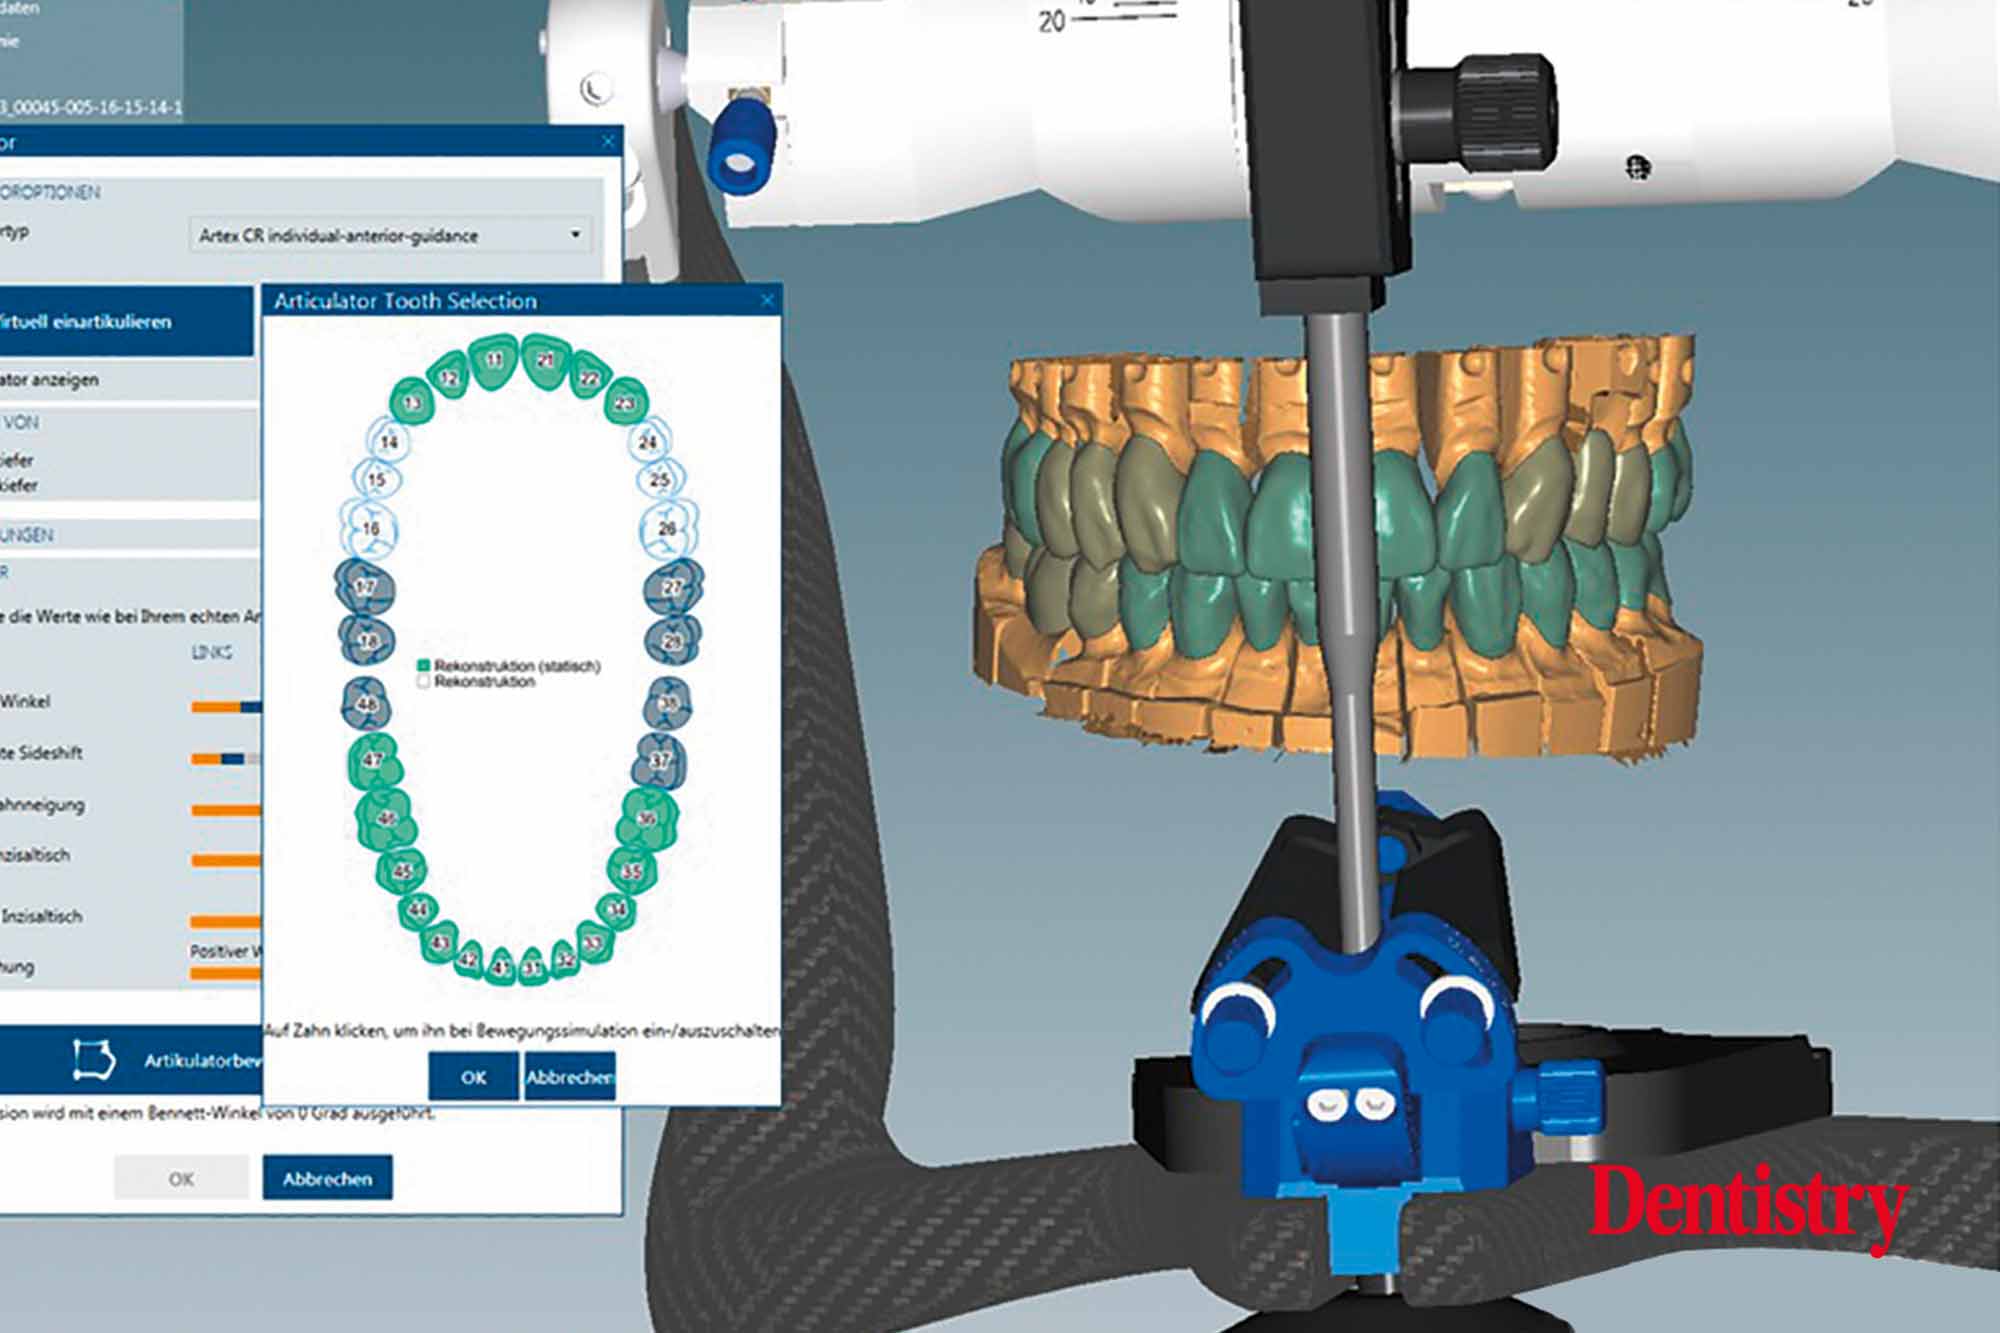

The scanned models were evaluated on a virtual 11 articulator. Temporary Ceramill PMMA (Amann Girrbach) transparent acrylic crowns were CAD planned (Figures 3a to 3d).

Patient data including condylar movements were recorded by the software. Using the Initial situation software’s customised incisal guide unit, the incisal guide pin was adjusted on the splitex plate to the desired cuspal inclinations on the virtual temporary crowns (Figure 4).

All patient parameters including condylar inclination were transferred to the Ceramill Artex articulator and the lateral and protrusive excursions were established while having no contact with the anterior teeth (Figures 5 to 8).